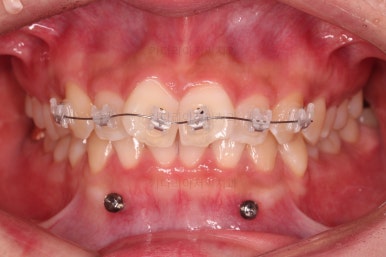

초진 시 입안의 모습입니다.

어금니 쪽은 약간 삐뚤긴 하지만 꼭 교정해야 할 정도는 아니고, 불편감 없이 비교적 잘 맞물리는 상태였습니다.

다만, 앞니ㅉㄱ이 공간이 부족해서 중간 치아들이 많이 회전되어있는데, 이를 환자분들의 표현에 따르면 "나비치아" 라고 부릅니다.

위아래 중간 앞니가 모두 나비치아처럼 되어있고요.

윗니가 아랫니보다 앞쪽으로 나와 있는 모습에 아래앞니가 윗니쪽으로 깊숙이 올라간 "과개교합" 양상을 보였습니다.

우선 윗니 앞니는 장치를 부착했고요.

아래 앞니는 장치 부착 이전에 아래로 앞니를 내려줄 미니스크류를 식립했습니다.

미니스크류가 단단하게 붙었을 시점에 아래 앞니도 장치를 부착하고요.

과개교합 개선을 위해서 미니스크류까지 힘을 줘서 아래 앞니를 내려줍니다.